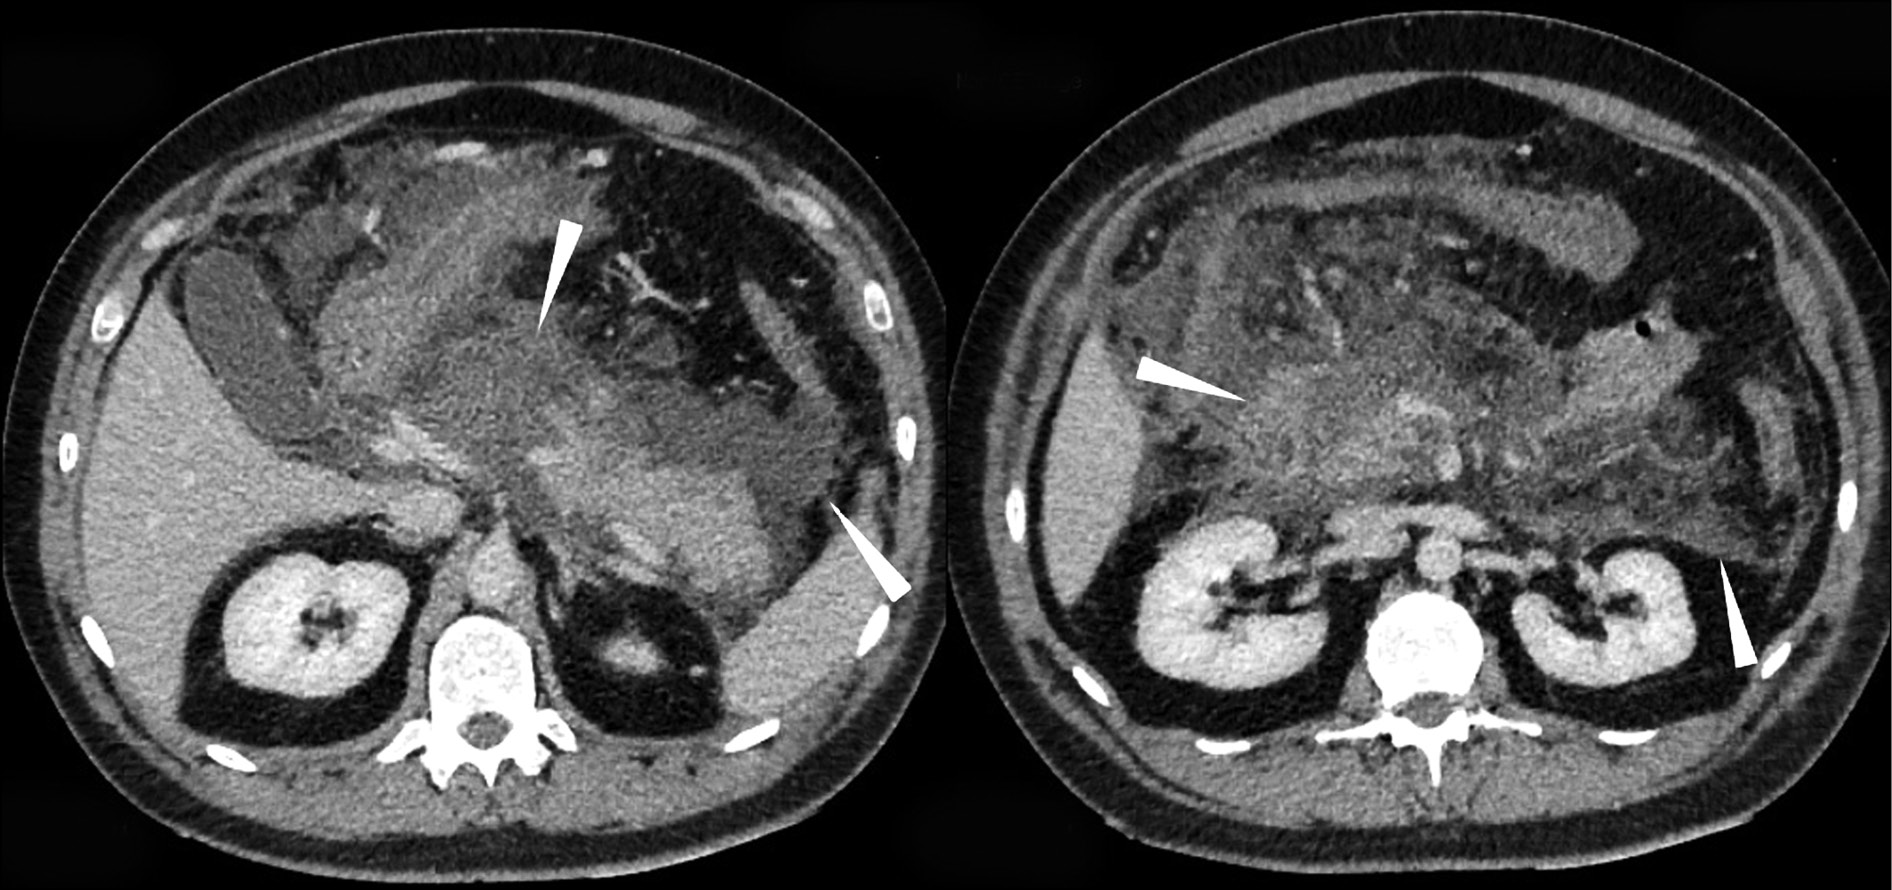

At the control AO CT scan (02/01; 02/02; 02/05/2018), the CT presentation showed no deterioration; the state of the pancreas and fluid accumulation along the gland contour in the area of the omental sac had changed; non-draining fluid accumulations in the retroperitoneal space were not detected (Fig. 3).

Fig. 3. Computed tomography of abdominal organs with intravenous contrast: infiltration and fluid accumulations in the peripancreatic adipose tissue, along the course of the amniotic fascia on the left, in the parenchyma of the head and body of the pancreas (arrows); drainage tube (zigzag arrow in the image on the left). In dynamics, the formation of a thin contrasting capsule along the course of the infiltration zone is noted.